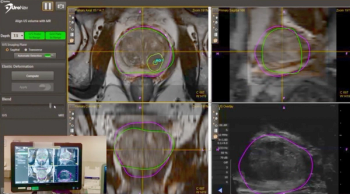

Jahan Aghalar, MD: The other role where sometimes a novel tracer may or may not impact outcomes is the treatment of oligometastatic disease. What do you do with a patient who has a slowly rising PSA [prostate-specific antigen]? You get the PET [positron emission tomography] Axumin scan, and you see 1 side of disease on PET L4. Do you go after it? Do you ablate it with radiation? Are we going to impact the trajectory of the disease? In those settings it brings up some interesting questions that will be brought up within the examination room and also hopefully within the realm of research.

Raoul Concepcion, MD, FACS: So Paul, Jahan brings up an interesting point. This concept-and I think this is going to become a bigger dilemma, especially for the busy clinical urologist-of oligometastatic disease at diagnosis. What do you do with the primary? The current definition by most people, although it’s not standardized, is less than 5 METs. Now we have the primary to deal with, we have mechanistically some different agents, and we have radiation. How do you see that playing out, basically with oligometastatic disease? Because we’ve talked about the deleterious effects of ADT [androgen deprivation therapy]. People necessarily don’t want to stay on long-term ADT, so for these patients, have you been using some of this next-generation imaging? How have you chosen? If you find somebody with a biochemical recurrence who, as Jahan said, maybe has an isolated lymph node that maybe you can go after. Are you going after them surgically and [spare] the patient ADT?

Paul Sieber, MD: Yes and no. If I have nodal disease, I’m looking at stereotactic radiation. If I have bone disease, I’m looking at stereotactic. In my most unusual cases-I had a guy with solitary metastasis to the testes, and now that he’s 2 years out with an undetectable PSA, with a rising PSA previously-I’ve got, oh my gosh. It’s all anecdotal data, but we’ve seen some real spiking responses in treating minimal metastatic disease with stereotactic treatments.

Raoul Concepcion, MD, FACS: I think it’s important for the viewers to remember that right now, fluciclovine, or Axumin, is currently approved. It’s approved in the United States, and it has to be a patient who has been diagnosed with prostate cancer and has been treated. It requires no other documentation. They don’t have to be CRPC. In a lot of markets, active surveillance is considered a treatment. Currently right now, as we sit here, that is the only FDA-approved biomolecular scan. As we talk about PSMA [prostate-specific membrane antigen], we think it’s going to be on the horizon. There are all kinds of issues obviously with PSA limitations and those types of things. But I think because most of us have discussed in this segment that this is an area, there’s a lot of attention and now there are obviously new therapies that are made available to our patients. Gordon, to your point, it is the early identification that’s important.